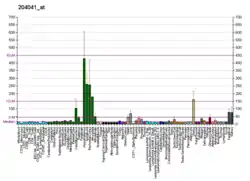

The protein encoded by this gene belongs to the flavin monoamine oxidase family. It is an enzyme located in the outer mitochondrial membrane. It catalyzes the oxidative deamination of biogenic and xenobiotic amines and plays an important role in the catabolism of neuroactive and vasoactive amines in the central nervous system and peripheral tissues. This protein preferentially degrades benzylamine and phenethylamine.[5] Similar to monoamine oxidase A (MAO-A), MAO-B is also involved in the catabolism of dopamine.[6]